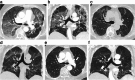

Results: Five patients were identified and analysed. All were females, with ovarian or breast cancer. Median age at O-ILD diagnosis was 71 (38-72) years old, with no smoking history. Median delay between treatment initiation and symptom occurrence was 12 (6-33) weeks. Pneumonitis severity assessed using the Common Terminology Criteria for Adverse Events V5 was Grade 3 (n = 4) or 2 (n = 1). CT-scan review (n = 3) described hypersensitivity pneumonitis reaction as a common pattern. Bronchioalveolar lavage (n = 4) revealed lymphocytic alveolitis. Treatments relied on olaparib discontinuation (n = 5) and glucocorticoid intake (n = 4), with no fatal issue. Safe re-challenge with PARPi occurred in two patients. Forty additional O-ILD cases were identified in the WHO VigiBase database, including one fatal case.

Conclusions: PARPi-ILD is a rare but potentially life-threatening disease, presenting as a hypersensitivity pneumonitis pattern within 3 months of PARPi initiation. Treatment primarily relies on medication discontinuation. Re-challenging with another PARPi could be considered.